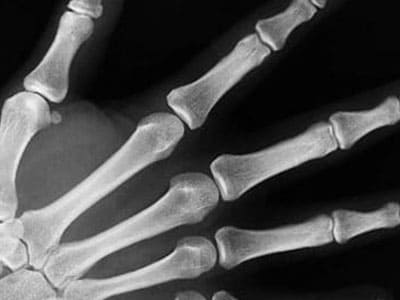

골다공증 예방

시서스는 골절의 치료와 회복을 도와 골다공증을 예방하는데 도움이 될 수 있습니다. 시서스에 관한 연구에 의하면 뼈가 손실되는 것을 줄여주고 골절된 뼈의 회복을 도운 것으로 알려졌습니다. 뼈가 형성되는데 도움을 주는 특정한 단백질 성분이 증가한 것인데요. 뼈의 건강을 유지하고 손상된 세포를 회복하는데 도움을 줄 수 있습니다.